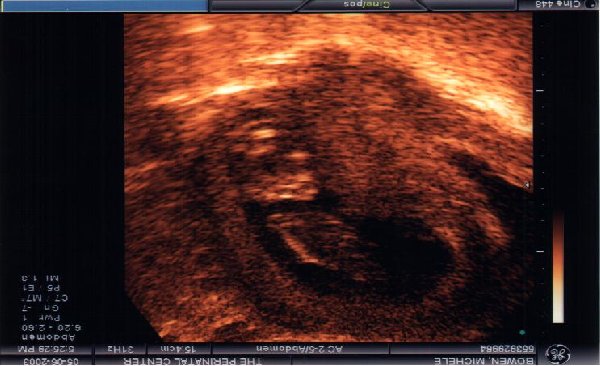

8-9 weeks 3rd doctors vist. you can start to see the eyes and face forming. :)